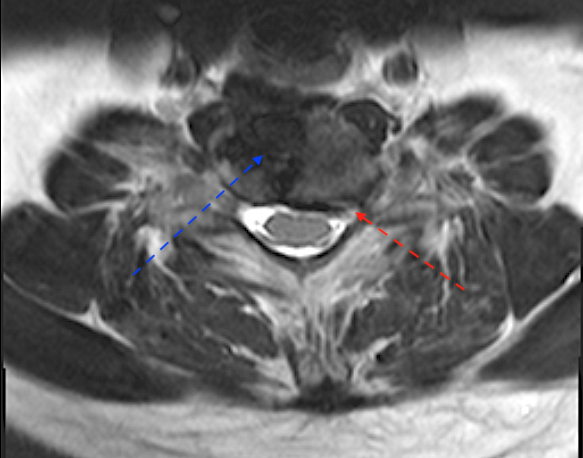

Obsérvese la ubicación de la prótesis

La flecha azul indica el hundimiento/resorción del platillo C7 en lado derecho, (la prótesis se ubicó muy lateral); el lado izquierdo (flecha roja) parece íntegro.

La flecha azul marca el espacio que ocupa la prótesis, la flecha roja la estenosis foraminal